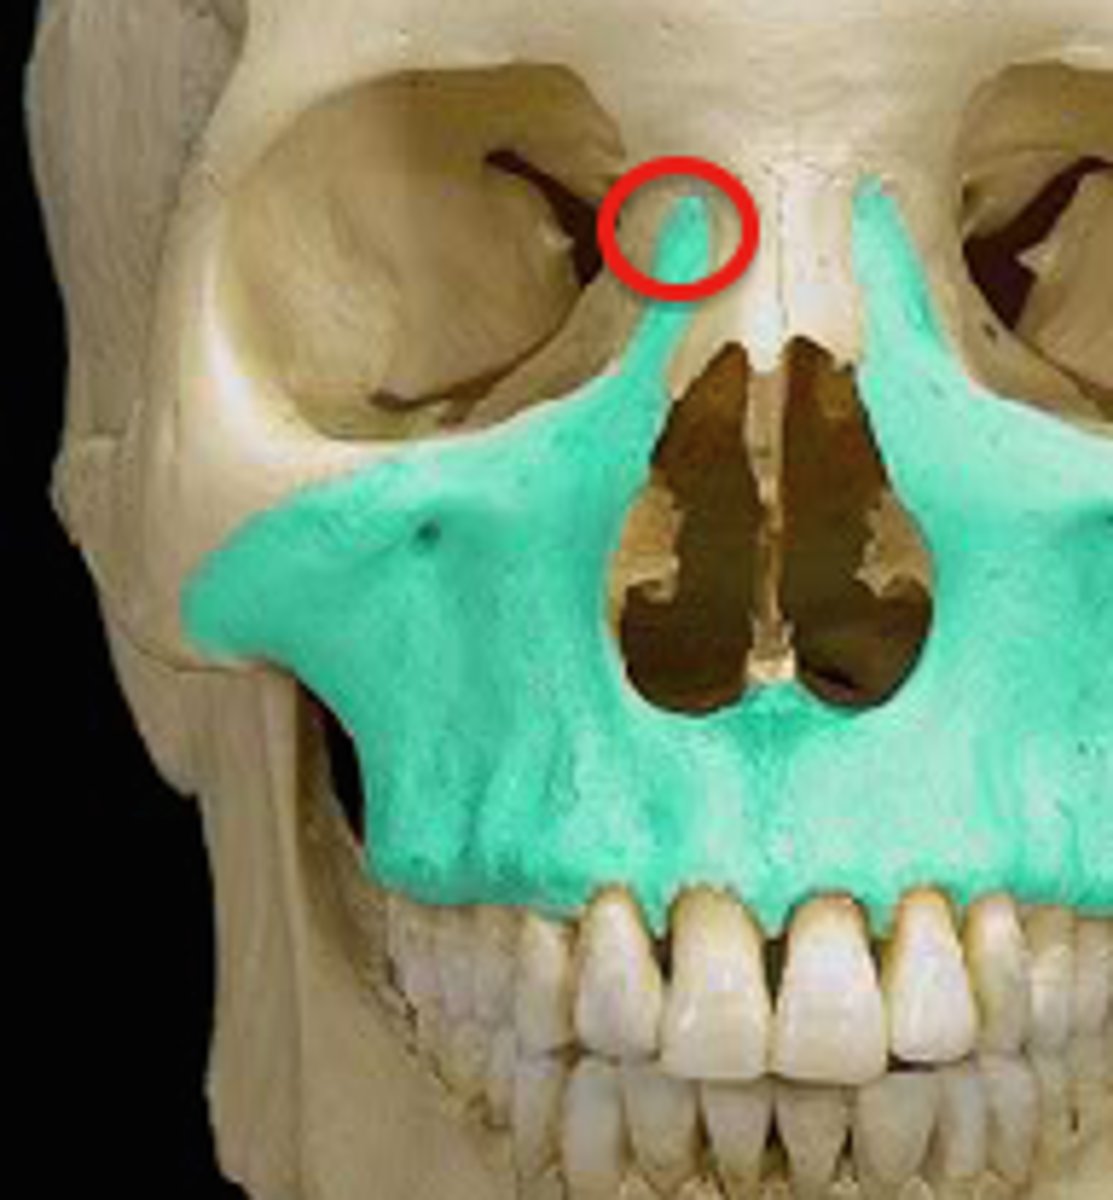

What is this and what does it do?

- Frontal process

- Extends up along the nose and the inner part of each infraorbital margin.

- Zygomatic process

- extends laterally from the body and touches the zygoma.

- Alveolar process

- Extends down to accommodate the teeth

- infraorbital foramen

- opening in the body , allows nerves and vessels to pass through

What is this and where is it located ?

- Palatine process

- flat plate extends medially above the mouth